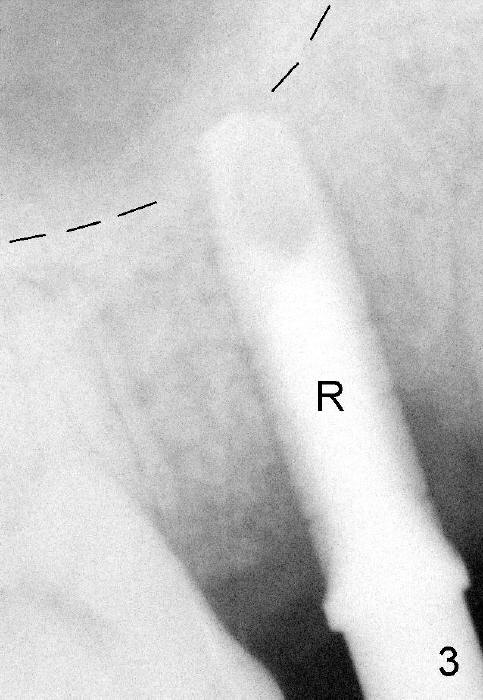

Osteotomes are used to form initial osteotomy, approximately 11 mm deep, 4 mm wide. Bicon reamers (Fig.3 R) are used to increase osteotomy while collecting autogenous bone; it appears that the sinus floor is partially penetrated (dashed line). After sinus lift (Fig.4 dashed line), a 5x14 mm cylindrical tissue-level implant is placed (I; arrowheads: sinus floor). There is no intraop nasal hemorrhage. Amoxicillin is prescribed postop (500 mg tid for 7 days). There is purulent, particulate discharge from the right nostril postop. One month later, the implant is loose and removed.